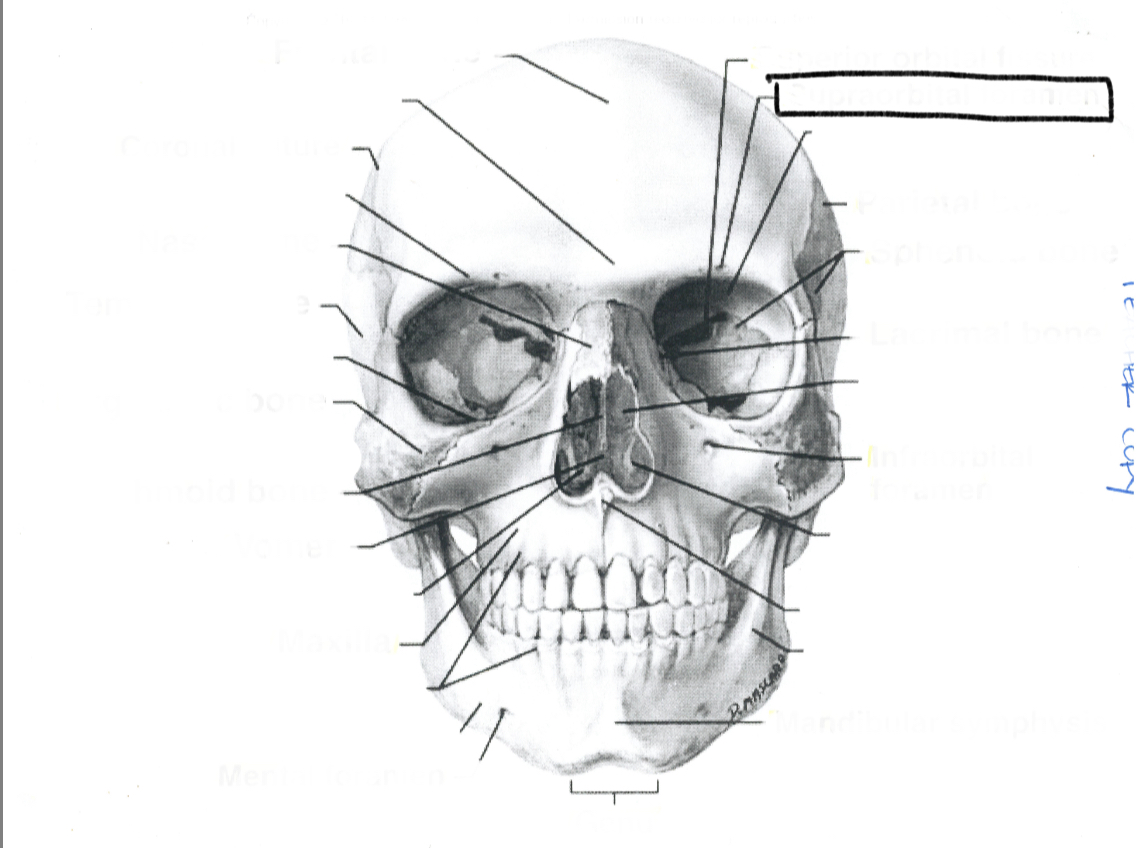

Coronal suture

Frontal bone

Coronal suture

Frontal bone